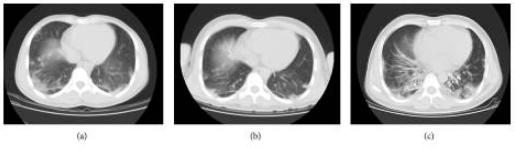

(ACA)、补体(C3,C4和CH50)、免疫球蛋白(IgM AG)、抗中性粒细胞胞浆抗体(ANCA)、抗核小体、抗环瓜氨酸肽(CCP)抗体和糖蛋白I(GPI)均在正常范围内。肌酸激酶水平正常(CK 32 U / L),铁蛋白水平显著升高(1016.9 ng / ml)。胸部的计算机断层扫描(CT)扫描显示ILD(图2a)。

图2 患者不同的阶段的CT扫描结果:(a)患者第一次来医院时出现渗出性病变。(b)治疗后,ILD逐渐好转。(c)当患者再次来到我们医院时,CT扫描显示晚期ILD。